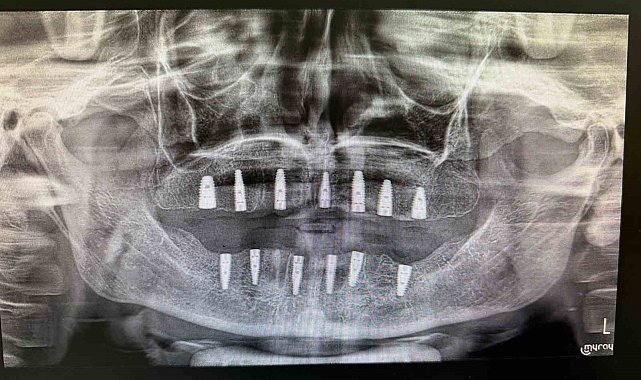

Bayburt Ağız ve Diş Sağlığı Merkezinde tamamen dişleri olmayan bir hastaya implant tedavisi uygulandı. Tedavi sonrası hasta, yeni dişlerine kavuştu.

Merkezde görevli Uzm. Dt. Sefa Merve Arıkan tarafından gerçekleştirilen ameliyatta hastaya 13 adet implant yerleştirildi.

Diş implantı, çene kemiğine yerleştirilen ve eksik dişlerin işlevini üstlenen yapay diş kökleri olarak biliniyor. Genellikle dişini kaybetmiş veya hiç dişi bulunmayan hastalara uygulanan bu yöntem, hem estetik görünüm hem de çiğneme fonksiyonunun yeniden kazanılmasını sağlıyor.

Tedavinin ardından hastanın, iyileşme süreci tamamlandığında normal beslenme ve konuşma yetilerini rahatlıkla kullanabileceği öğrenildi.